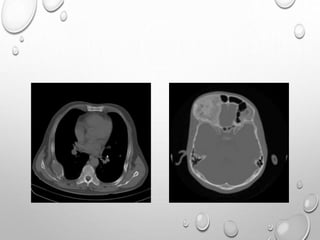

CORONAL COMPUTED TOMOGRAPHY SCAN OF THE ANKLE

DEMONSTRATING IRREGULARLY SHAPED PROTUBERANT BONE

(WHITE ARROW) IN THE MEDIAL ASPECT OF THE JOINT (A). AXIAL

COMPUTED TOMOGRAPHY SCAN OF THE ANKLE DEMONSTRATING

AN IRREGULARLY SHAPED PROTUBERANT BONE LESION OF THE

MEDIAL ANKLE JOINT, WITH A PORTION CONNECTED TO THE

ANTERIOR TALUS, AND A SECOND LESION MORE POSTERIORLY

LOCATED AND A DEFINED CLEFT (BLACK ARROWS) AT THE

INTERFACE (B).